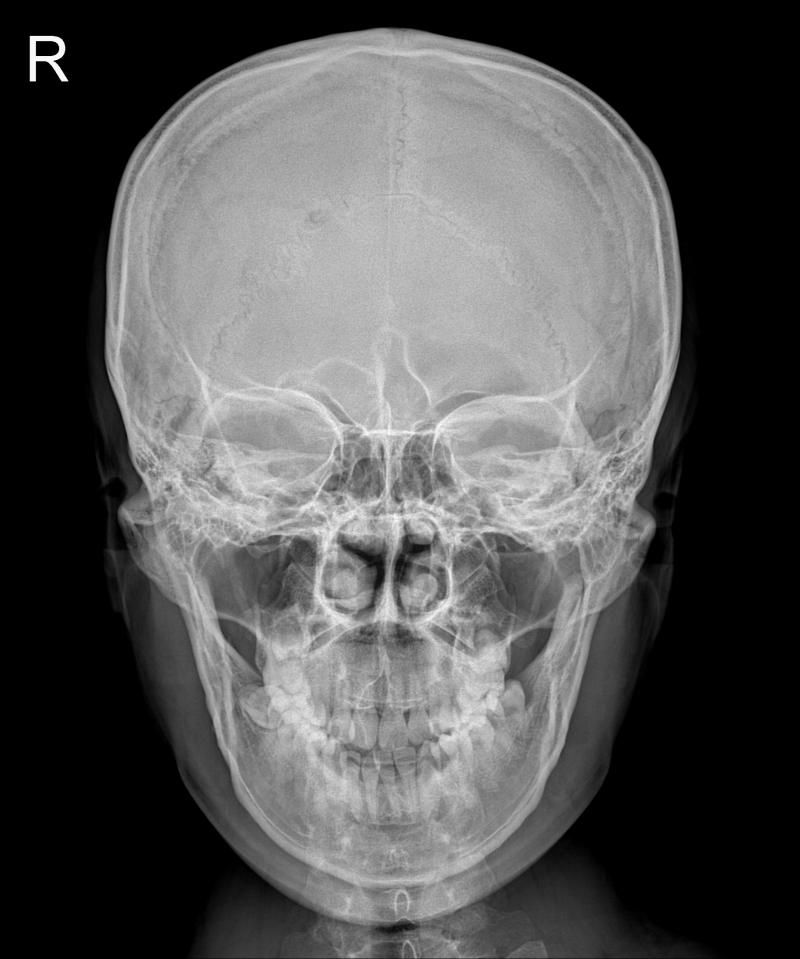

두번째 이미지가 비대칭이 더 심해보이는데

정확히 어떤 부분이 변했나요?

그리고 턱이 왼쪽으로 기울어진 것 맞나요?

아래사진이 약간 턱이 틀어진걸로보이긴하지만 엑스레이검사를하는 촬영각도나 환자의 움직임에의해서도 달라질수있으니 좀더 자세하게 확인하고싶다면 병원에서 전문의와 상담을받아보시길 바랍니다 감사합니다~!!!

아래 사진이 턱이 약간 왼쪽으로 기울어져 보이긴 합니다. 엑스레이 같은 경우 찍는 방향이나 각도에 따라 약간의 변형이 있을 수는 있는 검사 장치이기 때문에 정황한 상태는 병원에 방문하시어 전무가와 평가 받아보시는게 더 좋을 것으로 생각됩니다.

두번째 이미지에서 비대칭이 더 심해보인다면 특정 뼈의 크기나 형태가 달라졌거나 한쪽이 발달했거나 반대로 위축된 경우일 수 있습니다 예를들어 관자놀이나 이마의 형태가 다르게 나타날 수 있습니다

턱이 왼쪽으로 기울어졌다면 이난 하악골의 위치가 비대칭적으로 변화했음을 나타냅니다 턱의 기울어짐은 교합에도 영향을 미칠 수 있습니다

턱의 기울어짐은 턱관절이나 주변 근육의 불균형 또는 치아배열의 문제로 인해 발생할 수 있습니다 엑스레이에서 턱의 위치를 확인할 때 하악골의 각도나 위치를 비교하여 기울어짐을 평가할 수 있습니다

두 번째 이미지는 아래턱뼈가 좀 정렬이 안맞는 것 같습니다.

X-ray상 두 번째 이미지에 아래턱뼈가 좌측으로 휘어있습니다.

음영조절이나 색상반전을 해보시면 두 번째 이미지에 턱 부분의 실루엣이 좌측으로 넘어가 있을겁니다.

턱이 왼쪽으로 살짝 기울어져보입니다 이런 경우 턱 주변 근육의 긴장이나 비대칭으로 인해 한쪽이 더 발달하거나 긴장된 상태일 수 있습니다. 정확한 변화는 전문가의 평가를 받는 것이 좋습니다!